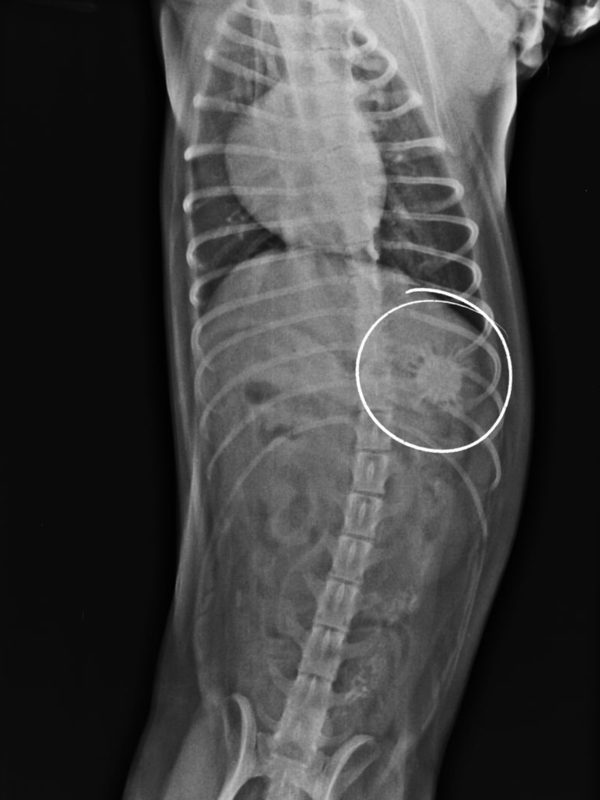

На RG в желудке собаки был обнаружен круглый предмет. Ветеринарный врач Клиники БАРС Анна Сергеевна Кашина приняла решение о немедленном проведении гастроскопии, т.к. инородное тело еще можно было извлечь при помощи эндоскопа. Находкой оказался мягкий резиновый мячик.